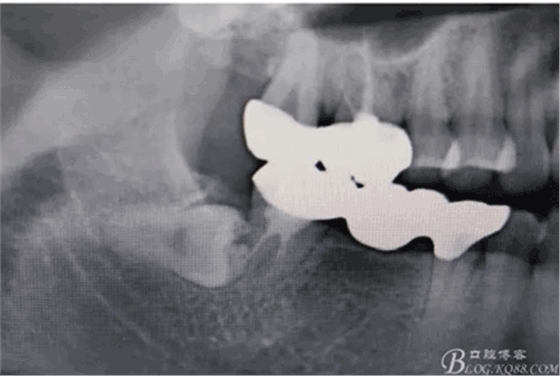

圖2.局部影像放大:48與47牙根 有部分重疊,顯示48牙冠位于47牙根的頰側(cè)或者舌側(cè),增加了損傷47全瓷牙的風(fēng)險。